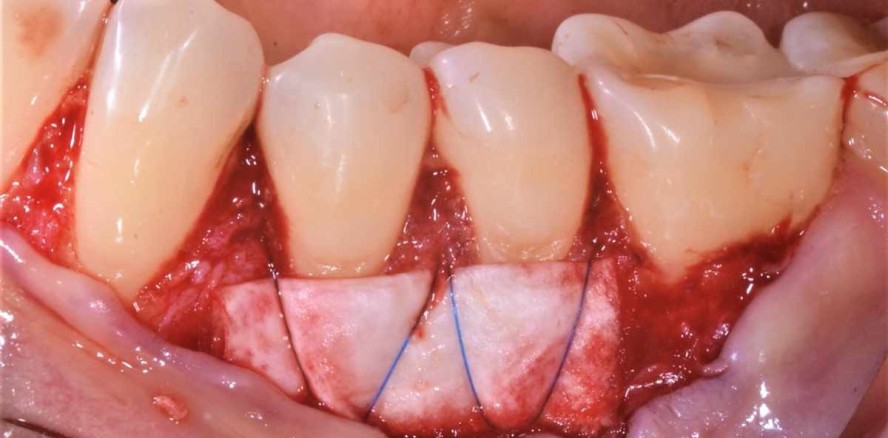

Die Operation erfolgte im Juli 2020 (Abb. 3). Als Zugang wurde ein modifizierter koronaler Verschiebelappen ohne Entlastungsinzisionen gewählt.

Eine intrasulkuläre Inzision und Mobilisierung erfolgte von distal 36 bis mesial 32. Es wurde Splitflap präpariert und einstrahlende Bänder mit einer oberflächigen und einer tiefen, scharfen Präparation abgesetzt.

Im nächsten Schritt wurde die Kollagenmembran (Smartbrane 30 x 20 mm) auf die erforderliche Breite von 15 x20 mm halbiert, in vernetzter Hyaluronsäure getränkt und zweifach gefaltet (hyaDENT BG, Regedent). Die Adaptation und Fixation auf den Wurzeloberflächen der Zähne 34 und 35 erfolgte dann mit überkreuzten Periostnähten (SABApol 6/0; Sabana). Die Membranpositionierung war dabei leicht apikal der imaginären Schmelz-Zement-Grenze, die anschließende Lappenrepositionierung dagegen weiter koronal mit Umschlingungsnähten. Alle Knoten wurden lingual positioniert.Die Patientin wurde antibiotisch abgeschirmt (Penicillin 750 mg, drei Mal täglich, N2).